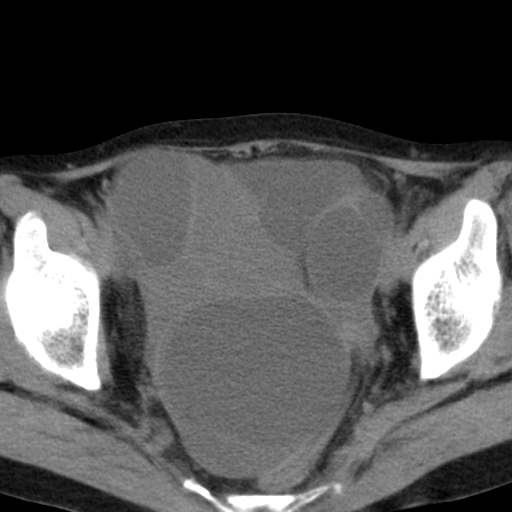

女,70,腹部间断性胀痛三月余

子宫宫腔及双侧附件积液,原因?

考虑卵巢囊腺瘤,不排除囊腺癌。

考虑卵巢囊腺瘤或囊腺癌。实质成分太多,考虑后者可能性大.

双侧卵巢粘液性囊腺癌,不多赘述。

考虑卵巢囊腺瘤;囊腺癌不能排除(理由:病人年龄较大,病灶外形欠规整、囊实相间,实性成分较多均支持囊腺癌)。要是能听听九目段老师的点评就好了!

年龄较大,囊实相间,实性成分较多均支持囊腺癌。